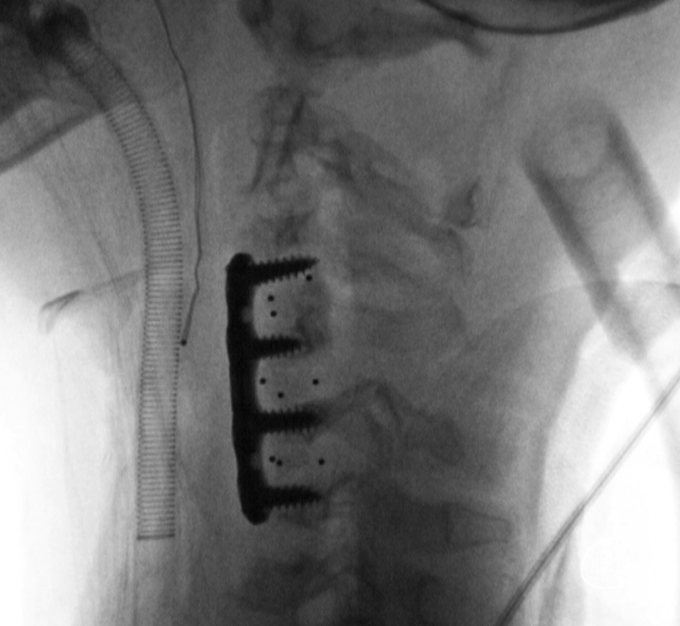

翻身行前路手术。采用左侧入路,同时切除肿瘤

C4-5置入牵开钉,可见椎体只能容纳一个牵开钉宽度

C3-4,C4-5,C5-6融合器放置完成

上钢板及螺钉,显示C5椎体无法良好复位

C5椎体内置入提拉螺钉,穿透椎体后壁,达到最佳提拉复位力量

旋转提拉套筒,显示C5椎体进一步向前复位

C5复位后置换置入前路螺钉